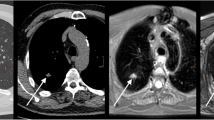

The screening results were false positive in 23 of 31 cases for MRI (74.2%) compared to 21 of 29 cases for LDCT (72.4%). In one case, a 6-mm nodule on MRI was not seen on LDCT. In another case, MRI could not depict that a 6-mm nodule was fat containing and thus definitely benign according to Lung-RADS (American College of Radiology 2017) (Fig. 1).

The advantages of MRI over non-enhanced LDCT are shown in Figs. 2 and 3. In both cases, nodules are hard to see on LDCT, because they are adjacent to pulmonary vessels. Both nodules are clearly visible on MRI.

37 of 38 solid nodules ≥ 6 mm (97.4%) were detected by MRI. The one missed nodule (6 mm) was fat containing, very flat, and located inside hypoventilated lung parenchyma. Three nodules with a size of 6–7 mm were calcified; all of them could be detected by MRI.